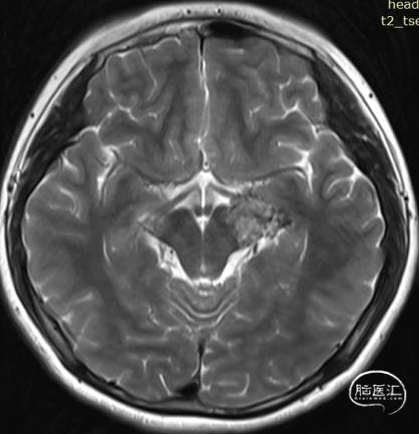

术前影像:

左侧海马旁回海绵状血管瘤。